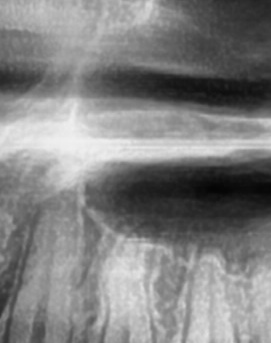

어금니 뒤 잇몸 부음의 문제는 사랑니가 원인이 되는 경우도 많은데 사랑니는 특히 현대인들의 경우 제대로 나오지 못하고 매복되는 경우가 많으며 완전히 나오지 않은 사랑니는 잇몸 속에서 자라면서 주변 잇몸을 자극할 수 있고, 일부만 노출되면 음식물이 끼면서 염증이 생기기도 하며 특히 어금니 뒤쪽 잇몸이 붓고 지속적으로 불편함을 느낀다면 사랑니로 인한 염증을 의심해 볼 수 있어요. 사랑니로 인한 문제의 경우 단순한 소염제나 구강 세정제로 해결되지 않고, 사랑니를 발치해야 잇몸 염증이 해결되는 경우가 많이 있어요

결론적으로는 통증이 심하거나 염증이 오래 지속되는 경우에는 치과를 방문해서 정확한 진단을 받는 것이 중요한데 단순한 잇몸 염증이라면 치석 제거와 항생제 치료로 호전될 수 있지만, 치주염이 진행된 경우라면 보다 적극적인 치료가 필요할 수 있어요. 만약 사랑니로 인해 잇몸이 자꾸 붓는다면 사랑니 발치를 고려해야 하겠고 사랑니가 완전히 매복되어 있다면 수술적인 방법으로 제거해야 할 수도 있어요. 특히 반복적으로 붓는다면 사랑니 검사를 받아보거나, 치과에서 정밀 검진을 통해 치주 상태를 확인하는 것이 필요하다는 점에서 어금니 근처의 잇몸이 반복적으로 불편하다면 꼭 치과를 찾아보시길 바라고 있어요